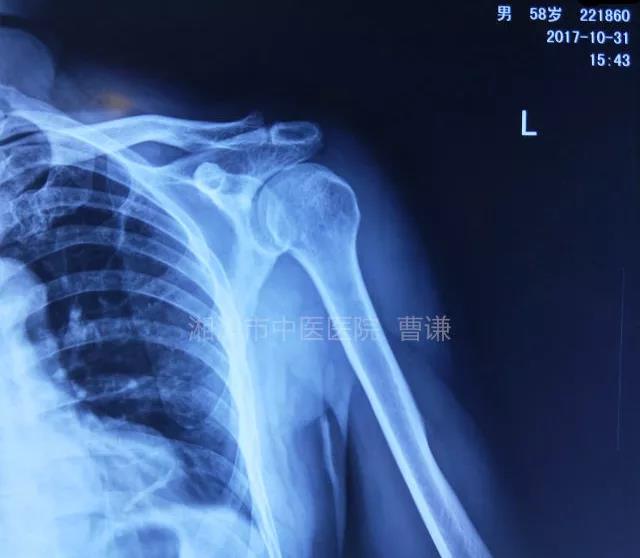

磁共振检查也完善了,还是报了个肩关节半脱位……影像科已经把坑挖好了……

接诊医生直接跳坑里了